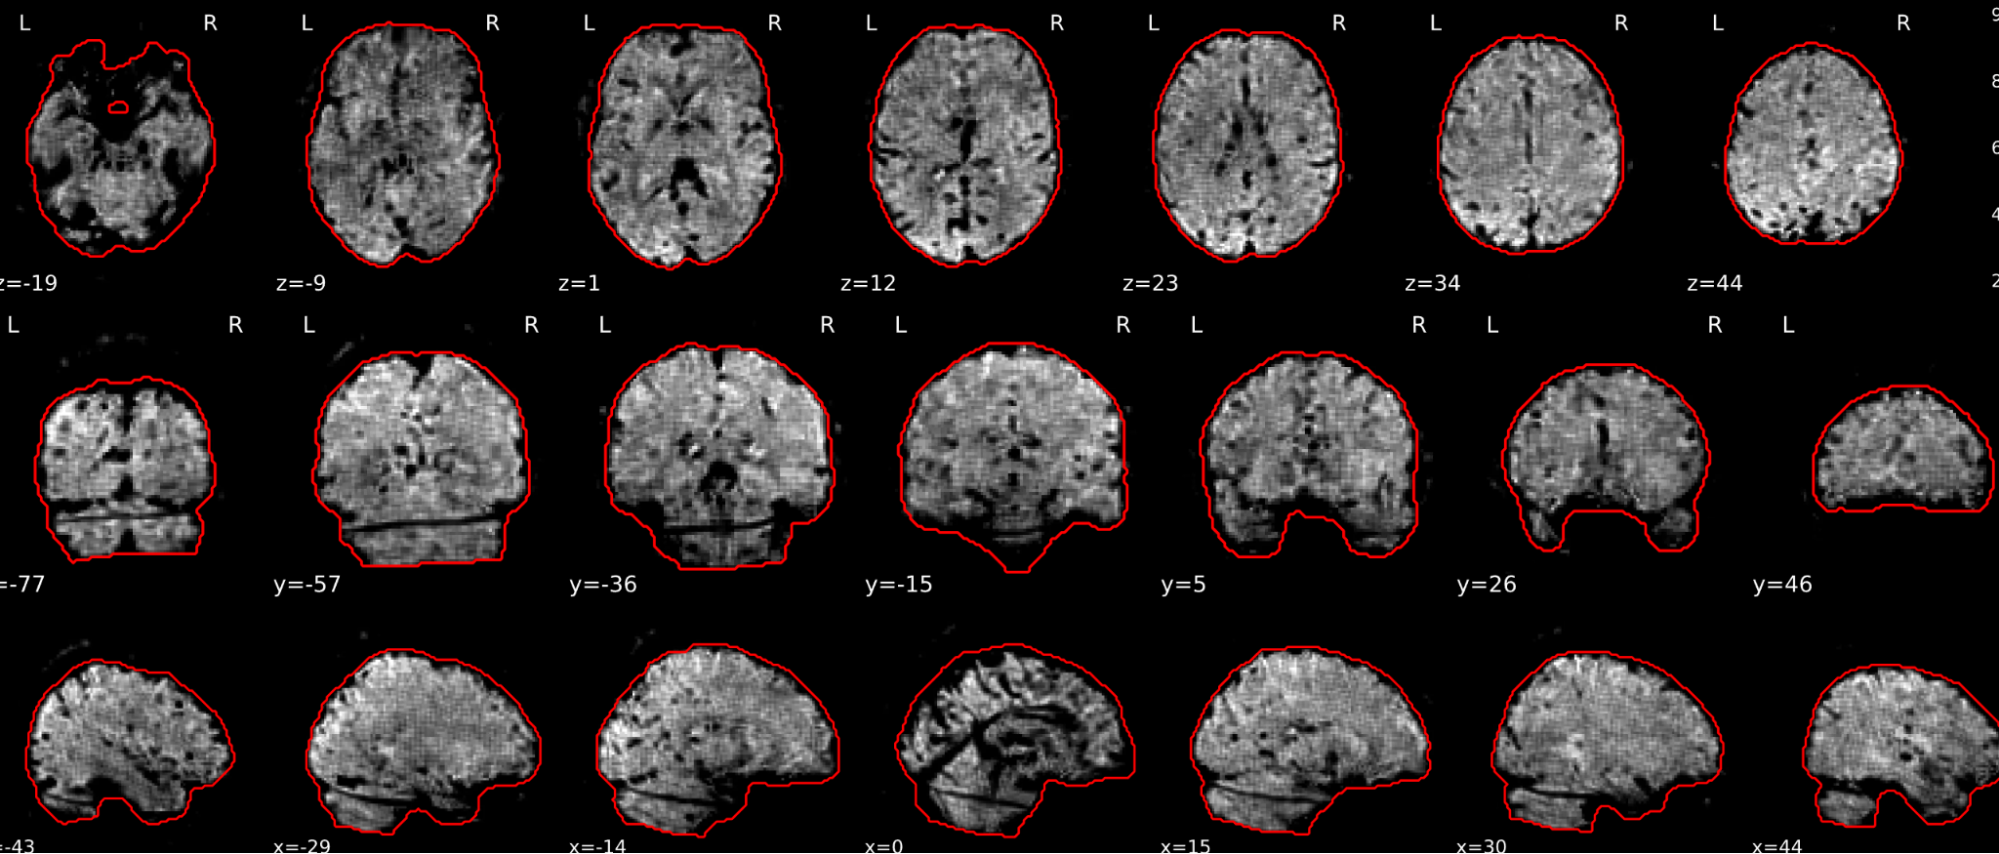

EPI tSNR

In the signal to noise ratio images of the resting state image the desired signal is compared to the amount of background noise. It is important to check all the views (sagittal, coronal, axial) because some artefacts (e.g., stripes) may be evident only in one particular view.

Example of a good subject

- Signal to noise is symmetrically distributed and there is no signal distortion

Example of a bad subject

- Asymmetry

- Potential signal distortion (might represent an artefact)

- Signal drop-out

- Stripes artefact

Clear large artefact (e.g., zebra stripes in example 1) are worth the exclusion of the subject. If you are unsure, check the other quality metrics for that subject to decide whether they should be excluded.

Summary

| good | bad |

|---|---|

| Symmetrical distribution of noise and signal | Asymmetry |

| No disruptions of the signal (no “black patches”) |

Potential signal disruptions (could be related to artefacts) |

| No stripes (sign of high motion) |

Signal drop |

| Stripe artefacts (“zebra” stripes due to motion) |